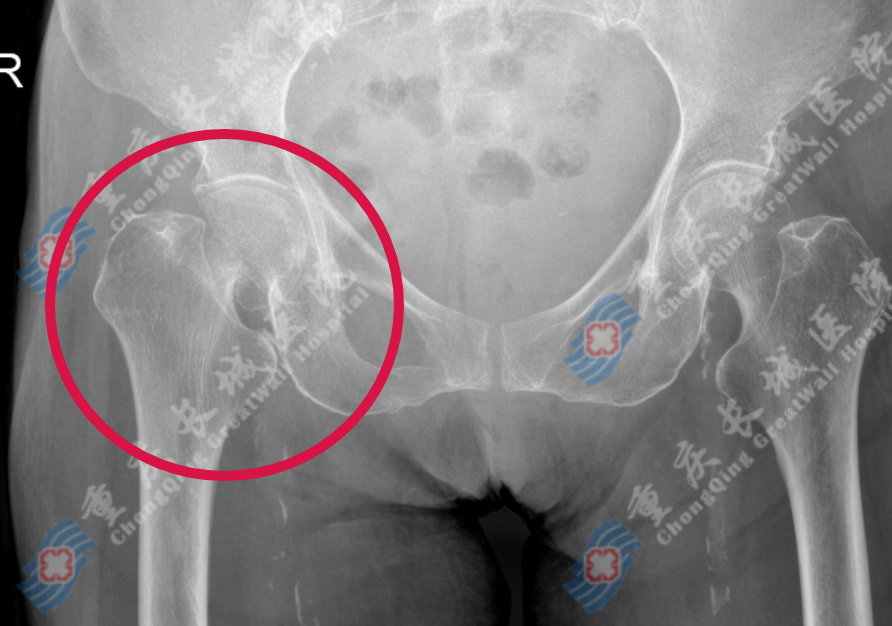

我院骨一科收治胡婆婆以后,经过系统的检查,确诊为:右股骨颈骨折;肝硬化(失代偿期);脾大;低蛋白血症伴胸、腹腔积液。胡婆婆年事已高,骨折再加上如此复杂的基础病,大大增加了治疗的难度,对我们的医生也是一个巨大的挑战。